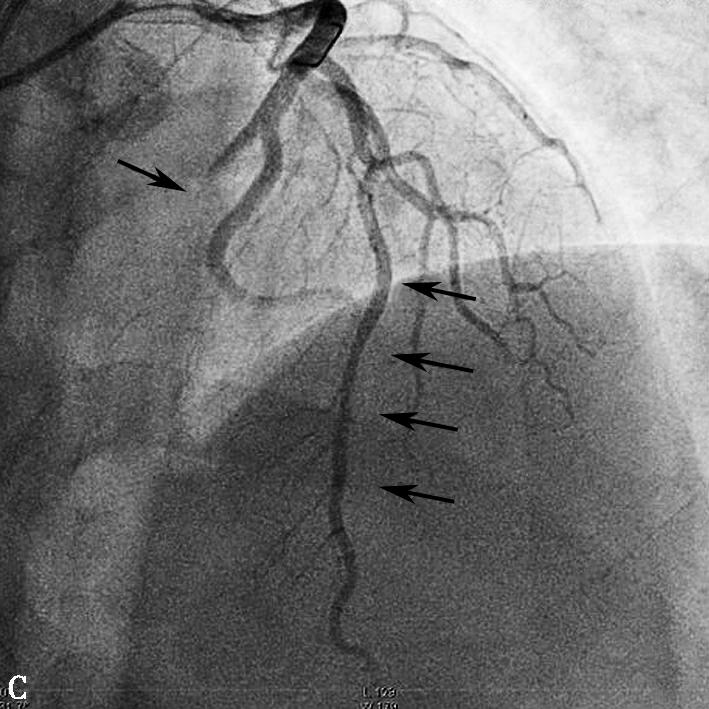

图1当地心电图及急诊PCI结果

A.当地市医院急诊心电图提示:Ⅱ、Ⅲ、aVF、V2~V5导联ST段弓背向上抬高;B.急诊造影提示:LAD开口闭塞,回旋支远段栓塞;C.PCI术后,LAD TIMI 2级,LCX远段血流未恢复